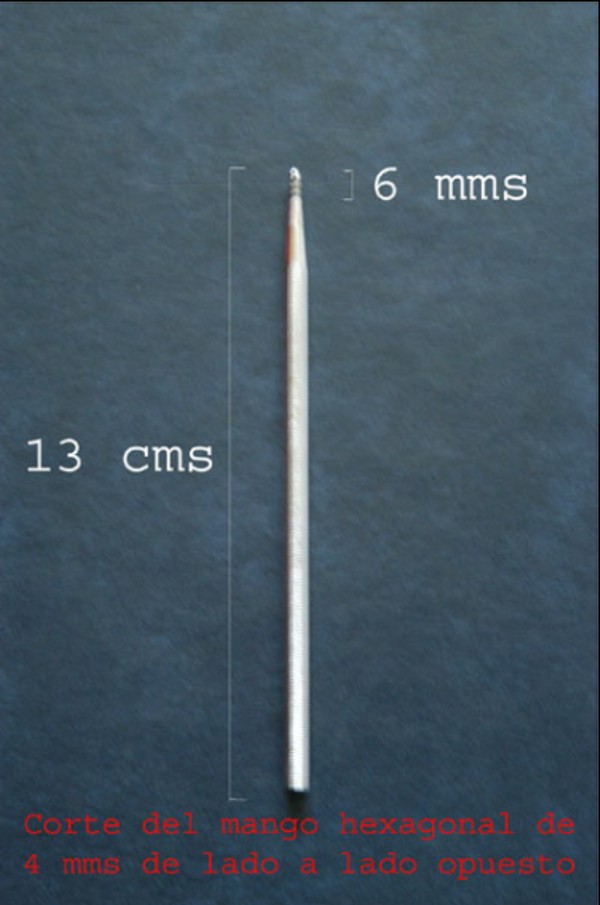

Las extracciones dentarias o EXODONCIAS, son habitualmente realizadas mediante la utilización de instrumentos denominados FÓRCEPS, los que instalados en el cuello de la pieza dentaria a extraer, son movidos de manera oscilante en el eje del diente, lográndose después de un corto período de tiempo, quitar al mismo de la cavidad ósea que lo aloja, en una operación que se denomina LUXACIÓN o AVULSIÓN. FÓRCEPS EN BOCA Esta AVULSIÓN, se produce debido a que el hueso es elástico. Sin embargo , gran parte de las veces esa elasticidad no es suficiente y se parte o rompe la «corteza ósea» que rodea al diente, en su región más cercana a la «zona cortante» del mismo.Esa ruptura o fractura, es favorecida por el uso de los Fórceps, dado que sus «mordientes» se sitúan muy cerca de del hueso. .FÓRCEPS ROMPIENDO LA TABLA TABLA ROTA La idea de crear un instrumento que impida dicha fractura, se basa en la certeza de que cuanto más adentro del diente, y cuanto más cerca de la punta del diente, se efectúe la fuerza de AVULSIÓN, menos posibilidades de fractura existirán por una simple cuestión de física básica: CUANTO MÁS LARGO SEA EL BRAZO DE POTENCIA DE UNA PALANCA, MENOS ACCIÓN TENDRA EL BRAZO DE RESISTENCIA….POR LO TANTO SERÁ NECESARIA MENOS POTENCIA PARA VENCER LA RESISTENCIA… O SEA, CON MOVIMIENTOS MAS DELICADOS , LOGRAREMOS EL MISMO EFECTO. ESQUEMA DE DIENTE MOSTRANDO LA ACCIÓN DE LAS FUERZAS DE UN FÓRCEPS. ESQUEMA DE DIENTE MOSTRANDO LA ACCIÓN DE FUERZAS DE UN AIDA Cuando la especialidad IMPLANTOLOGÍA, no se había desarrollado tal como ahora la conocemos, la fractura de esa «corteza ósea» denominada TABLA EXTERNA O INTERNA del PROCESO ALVEOLAR, carecía de importancia ya que la cicatrización se produce irremediablemente en ausencia de infecciones Sin embargo, a la luz de los conocimientos actuales, la preservación de dichas TABLAS, son de capital importancia para la realización de un IMPLANTE INMEDIATO(Implante colocado en el mismo acto quirúrgico que la extracción), y para el logro de su INTEGRACIÓN Y ESTÉTICA futura. Es por eso que exponemos ante las autoridades competentes, la idea de patentar un instrumento como el que denomino: AVULSIONADOR INTRADENTARIO ATRAUMÁTICO …cuyas características principales son: MATERIAL: ACERO QUIRÚRGICO 316 LONGITUD TOTAL:13 mm PUNTA ACTIVA: 6 mm FORMA DE PUNTA ACTIVA: HELICOIDAL DECRECIENTE DOS GROSORES DE PUNTA. INSTRUMENTO AD HOC Por acción de las espiras , el instrumento se fija en las paredes del canal dentario, produciendo un anclaje que permite la AVULSIÓN. CRESTA ÓSEA COMPLETAMENTE CONSERVADA

DIBUJO TÉCNICO DEL INSTRUMENTO